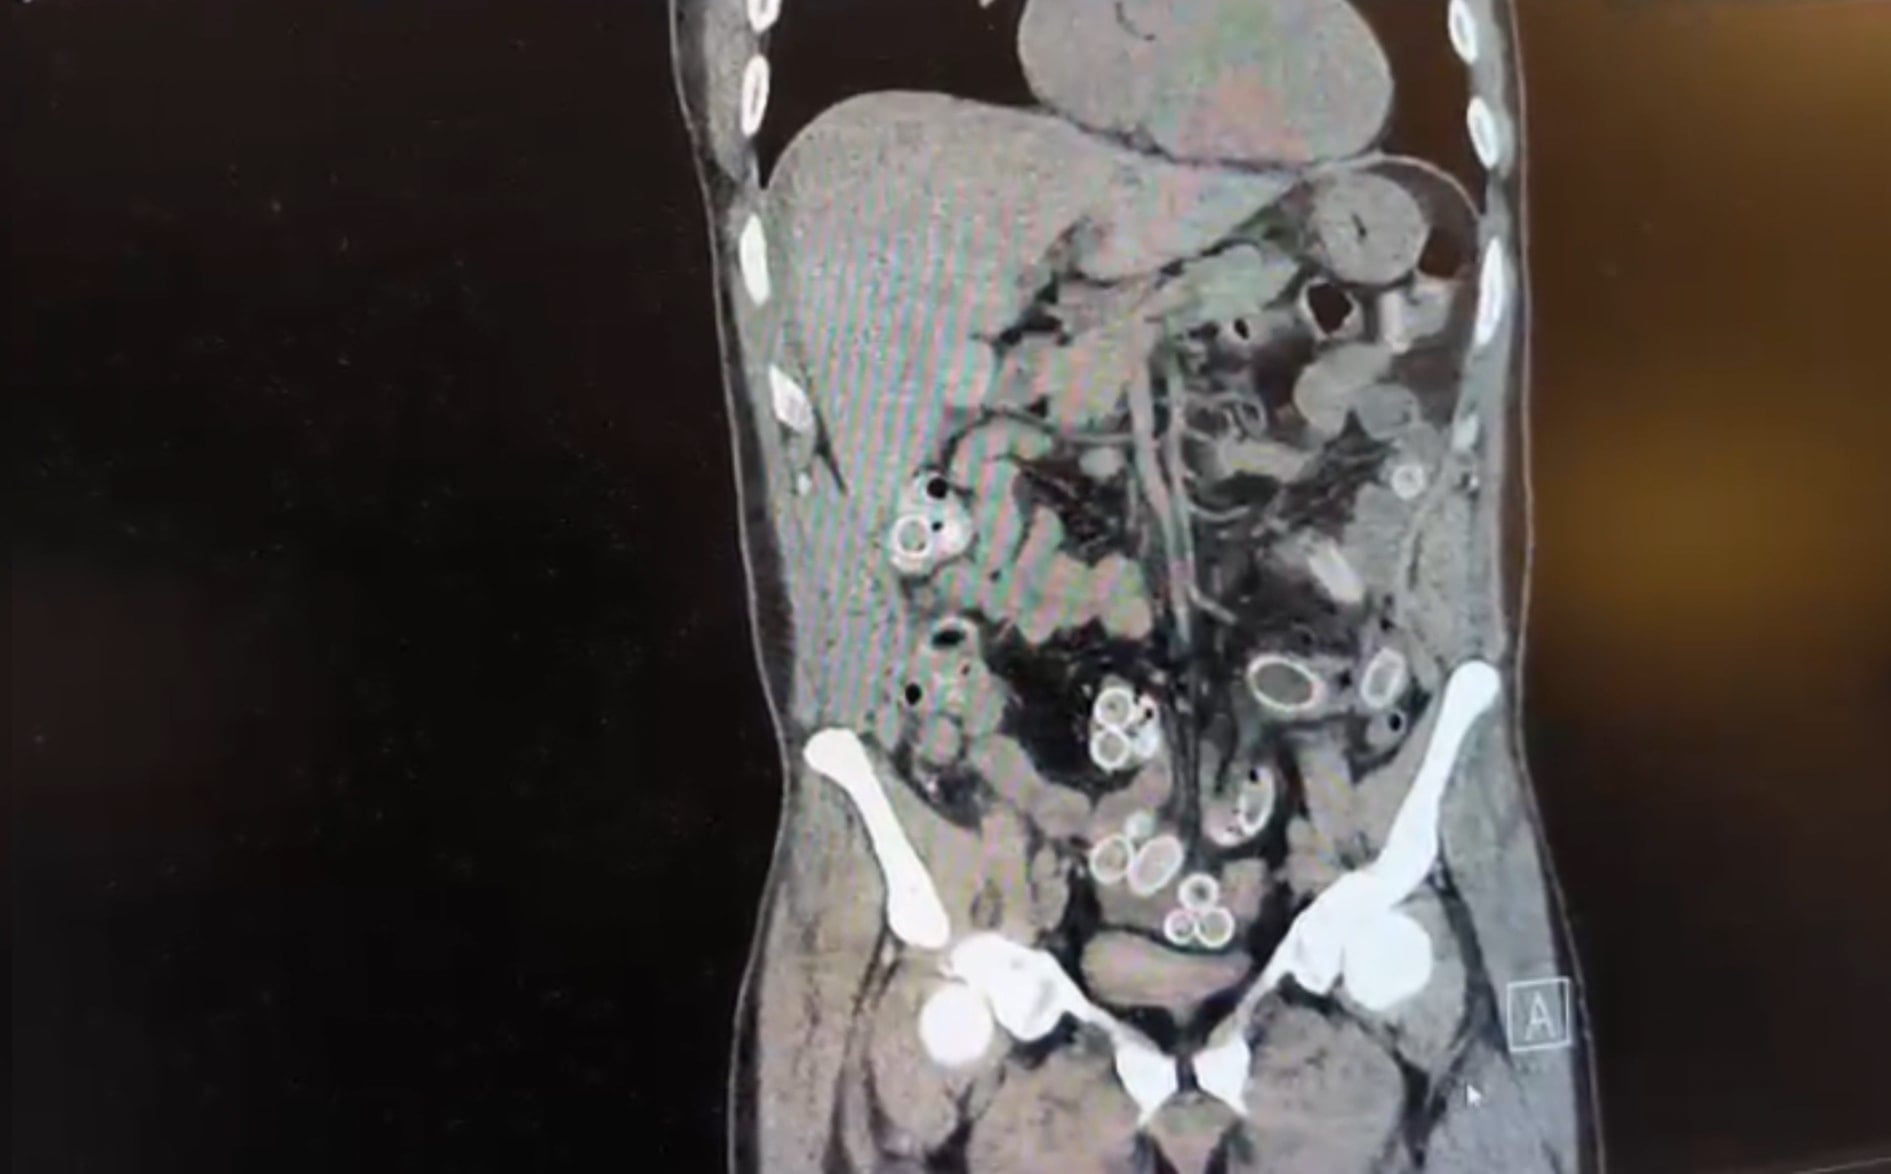

Yapılan muayenenin ardından çekilen tomografide Cüneyt Ç.’nin mide ve bağırsaklarında yabancı maddeler tespit edildi. Bunun üzerine hastane durumu polis ekiplerine bildirdi. İhbar sonrası Beşiktaş Asayiş Büro Amirliği ekipleri konuyla ilgili çalışma başlattı.

Doktorların değerlendirmesi sonrası ameliyata alınan Cüneyt Ç.’nin mide ve bağırsaklarından kapsül halinde toplam 49 adet esrar macunu çıkarıldı. Kapsüllerin toplam ağırlığının 259,7 gram olduğu öğrenildi. Şüpheliye ait bir cep telefonu da inceleme yapılmak üzere polis ekiplerine teslim edildi.